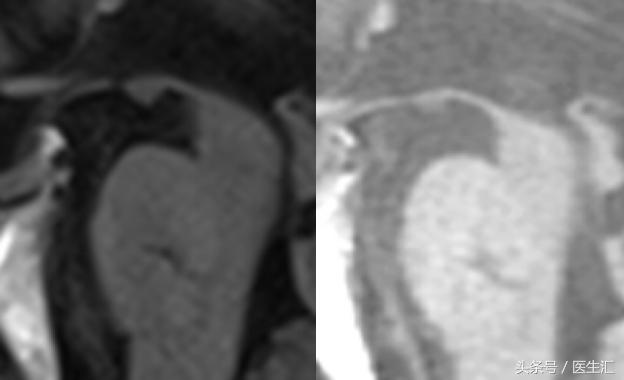

影像检查

诊断:

进行性核上性麻痹-帕金森型